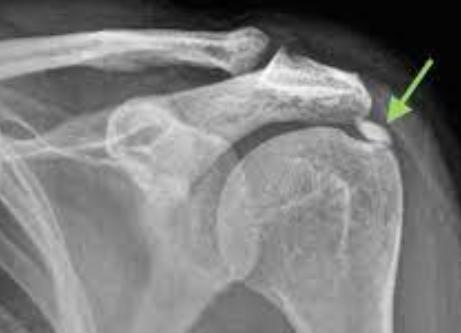

어깨 석회질은 어깨 주변에 발생하는 석회 침착을 말합니다. 이는 어깨의 연조직에 침착된 석회가 통증을 일으키는 주요 원인이 됩니다. 석회질은 통상적으로 회전근개 건에 주로 나타나며, 부상, 염증 또는 연령과 같은 여러 원인에 기인할 수 있습니다.